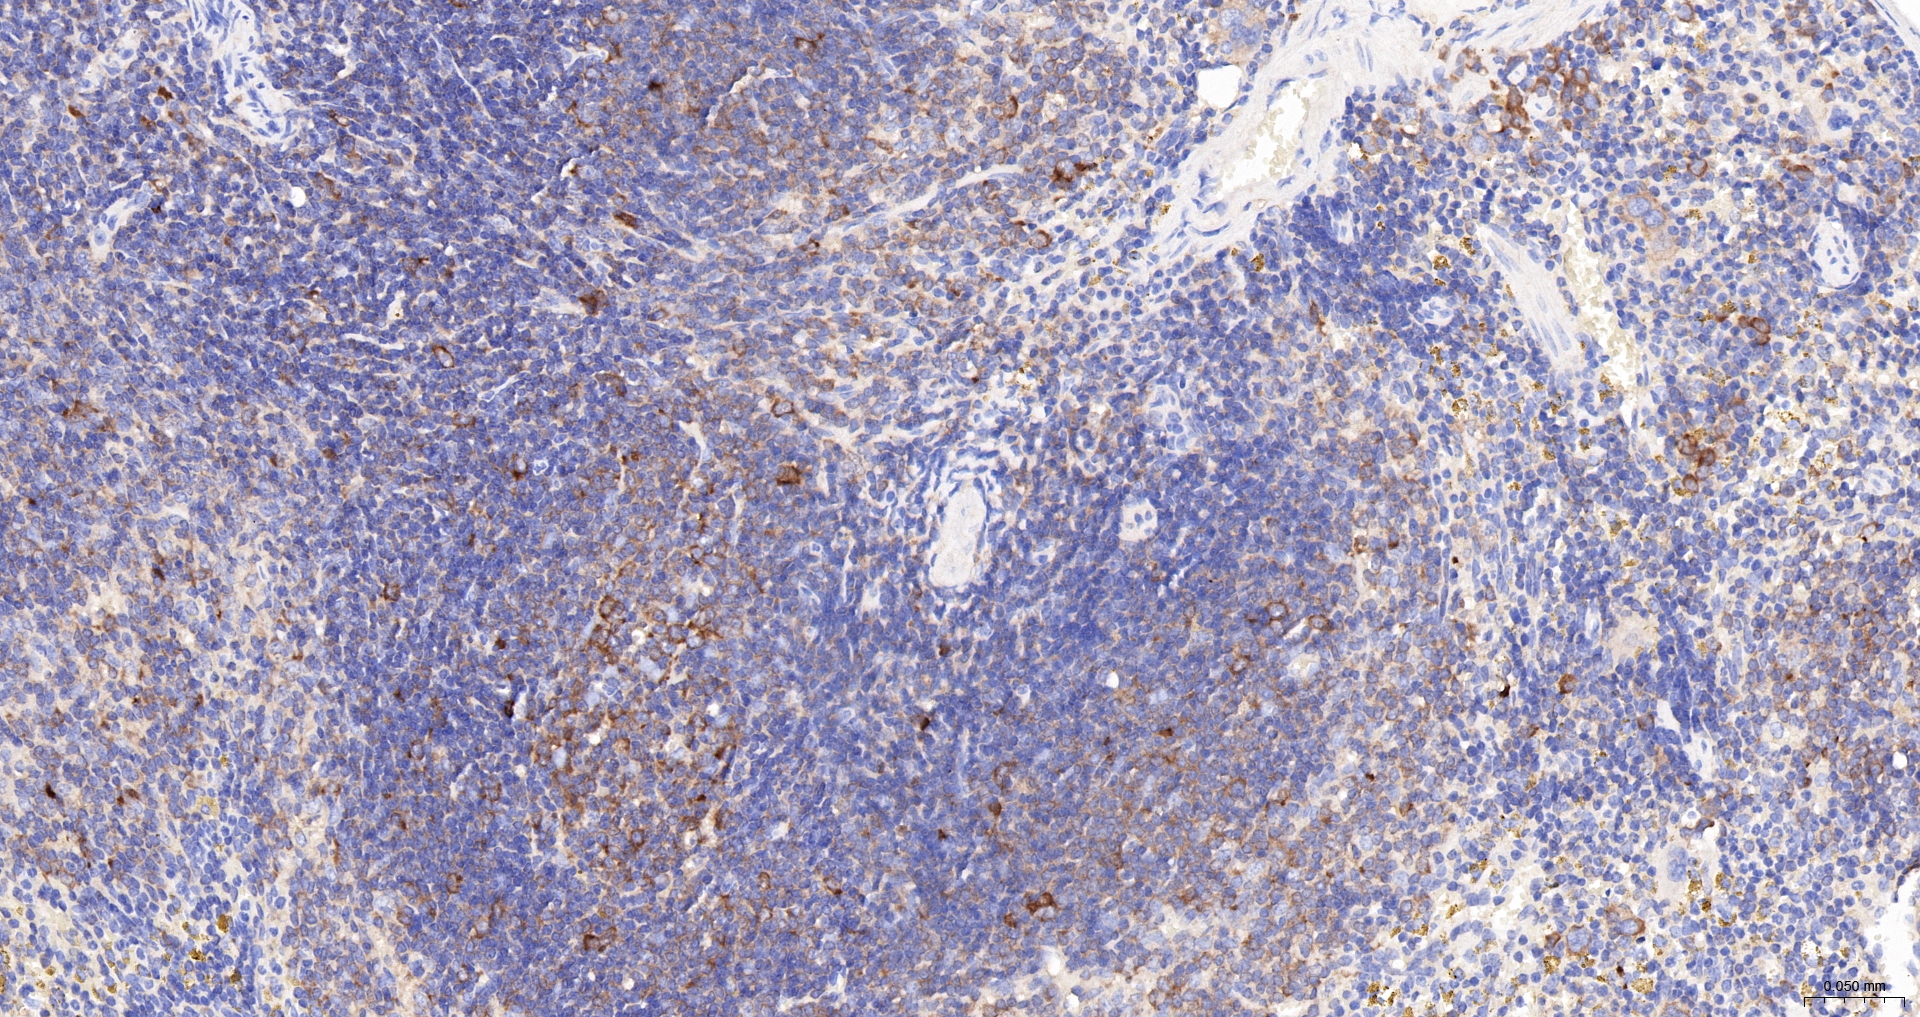

IHC-P IHC-P1:100-500